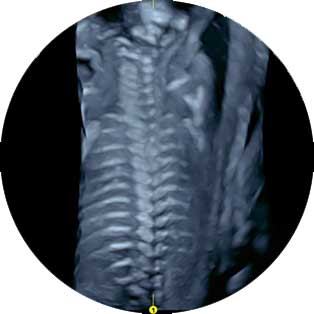

Οι βασικές τομές που λαμβάνονται είναι η διακοιλιακή και η διαπαραγκεφαλιδική τομή, όπου ελέγχεται μια πλειάδα ανατομικών τμημάτων του εγκεφάλου, όπως οι πλάγιες κοιλίες, το διαφανές διάφραγμα, οι θάλαμοι, η παραγκεφαλίδα, ο σκώληκας η 4η κοιλία του εγκεφάλου και, όταν απαιτείται, λαμβάνονται επιπλέον τομές, όπως η οβελιαία και η στεφανιαία τομή για έλεγχο των κοιλιών του εγκεφάλου και του μεσολοβίου σώματος.